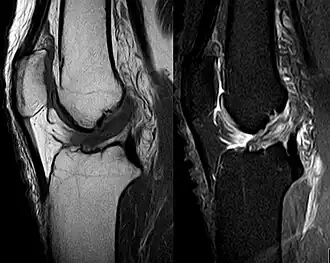

MRI shows normal signal of both cruciate ligaments (arrows)